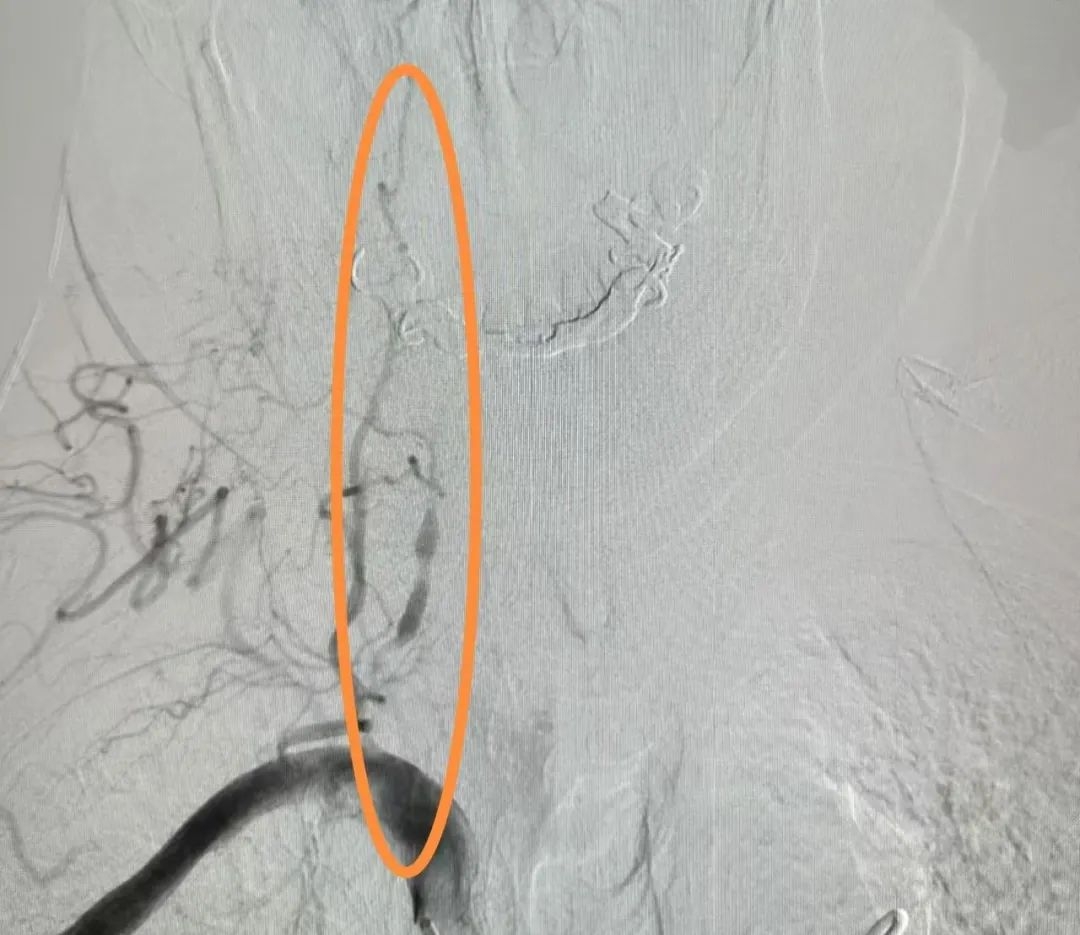

介入導(dǎo)管室內(nèi),彭勇精細操作,通過局部麻醉和股動脈穿刺技術(shù),將造影劑緩緩注入血管內(nèi),使腦部血管顯影,最終發(fā)現(xiàn)郭大叔右側(cè)椎動脈彌漫性重度狹窄,雙側(cè)頸內(nèi)動脈多發(fā)中度狹窄。這一結(jié)果為患者后續(xù)藥物治療及病情評估提供了充分的臨床依據(jù)。 “右側(cè)椎動脈全程多處重度狹窄,呈串珠樣,無法放置支架,其它中度狹窄暫時不需要放支架,病情特殊無法行介入治療,暫時以保守治療為主,注意隨訪……”病房內(nèi),彭勇言簡意賅地向家屬交代了手術(shù)結(jié)果,分析了病情走向,一番話讓家屬連連點頭。